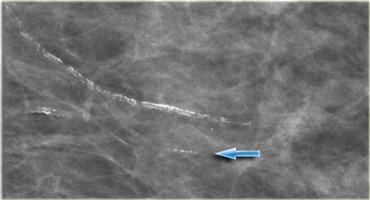

Chúng có dạng tuyến tính hoặc tạo thành hai đường song song, thường liên quan rõ ràng đến mạch máu.

Bên trái là hình ảnh vôi hóa mạch máu điển hình.

Nếu chỉ một thành của mạch máu bị vôi hóa (mũi tên), vôi hóa có thể giả dạng vôi hóa trong ống dẫn sữa, nhưng thông thường chẩn đoán khá rõ ràng.